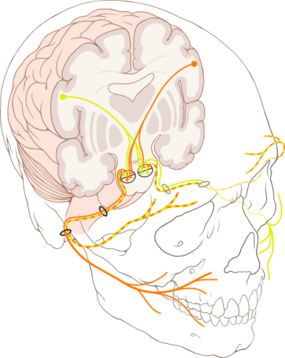

Innervation

The sensations registered by the human nose derive from the first two branches of the trigeminal nerve (cranial nerve V). The nerve listings indicate the respective innervation (sensory distribution) of the trigeminal nerve branches within the nose, the face, and the upper jaw (maxilla).

- Ophthalmic division innervation

- Lacrimal nerve – conveys sensation to the skin areas of the lateral orbital (eye socket) region, except for the lacrimal gland.

- Frontal nerve – conveys sensation to the skin areas of the forehead and the scalp.

- Supraorbital nerve – conveys sensation to the skin areas of the eyelids, the forehead, and the scalp.

- Supratrochlear nerve – conveys sensation to the medial region of the eyelid skin area, and the medial region of the forehead skin.

- Nasociliary nerve – conveys sensation to the skin area of the nose, and the mucous membrane of the anterior (front) nasal cavity.

- Anterior ethmoid nerve – conveys sensation in the anterior (front) half of the nasal cavity: (a) the internal areas of the ethmoid sinus and the frontal sinus; and (b) the external areas, from the nasal tip to the rhinion: the anterior tip of the terminal end of the nasal-bone suture.

- Posterior ethmoid nerve – serves the superior (upper) half of the nasal cavity, the sphenoids, and the ethmoids.

- Intratrochlear nerve – conveys sensation to the medial region of the eyelids, the palpebral conjunctiva, the nasion (nasolabial junction), and the bony dorsum.

The supply of parasympathetic nerves to the face and the upper jaw (maxilla) derives from the greater superficial petrosal (GSP) branch of cranial nerve VII, the facial nerve. The GSP nerve joins the deep petrosal nerve (of the sympathetic nervous system), derived from the carotid plexus, to form the vidian nerve (in the vidian canal) that traverses the pterygopalatine ganglion (an autonomic ganglion of the maxillary nerve), wherein only the parasympathetic nerves form synapses, which serve the lacrimal gland and the glands of the nose and of the palate, via the (upper jaw) maxillary division of cranial nerve V, the trigeminal nerve.